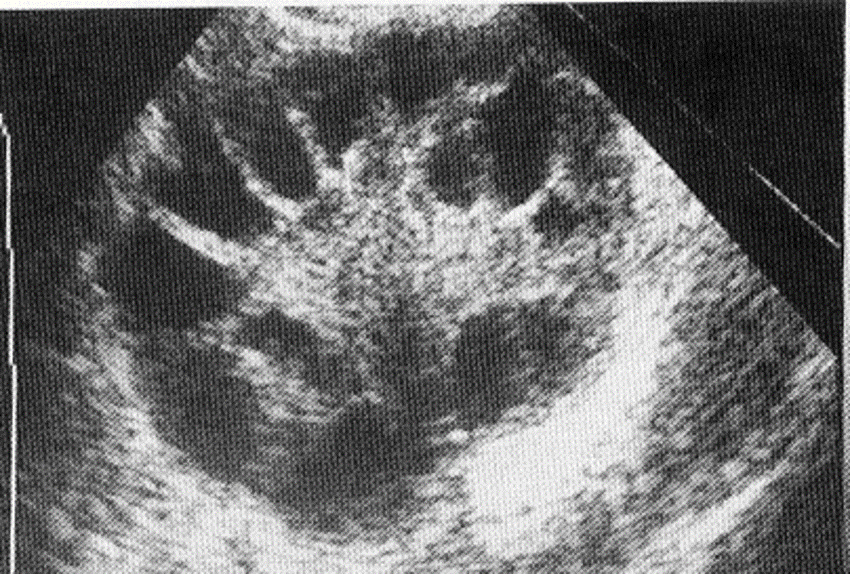

peritoneal inclusion cysts

endometriosis